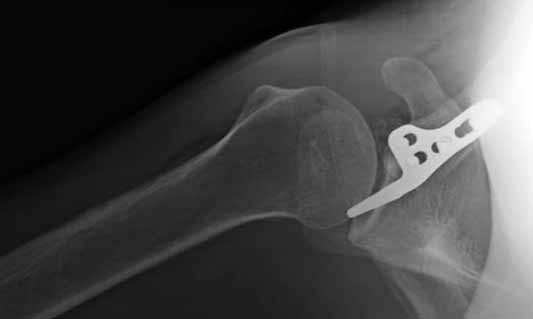

Но это не помешало успешно пациента прооперировать.

Еще раз спасибо Вам и всем форумчанам за внимание к теме и помощь.

1.JPG

60KB (62415 bytes)